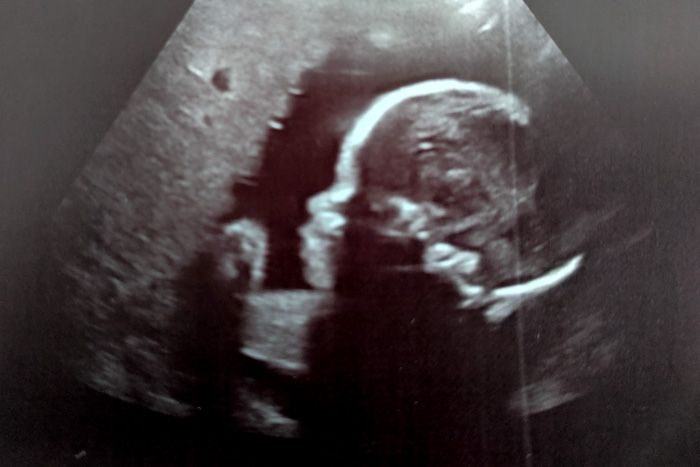

26 weeks with Emelia: It’s time for more ultrasounds, but at least I get to see how fluffy her cheeks get

I got to see Queso again because I needed a blood pressure check yesterday. My BP was 133/83, so it was slightly elevated even on my blood pressure meds, but the PA I saw in my doctor’s absence said it was OK. Baby was measuring a little over a week…